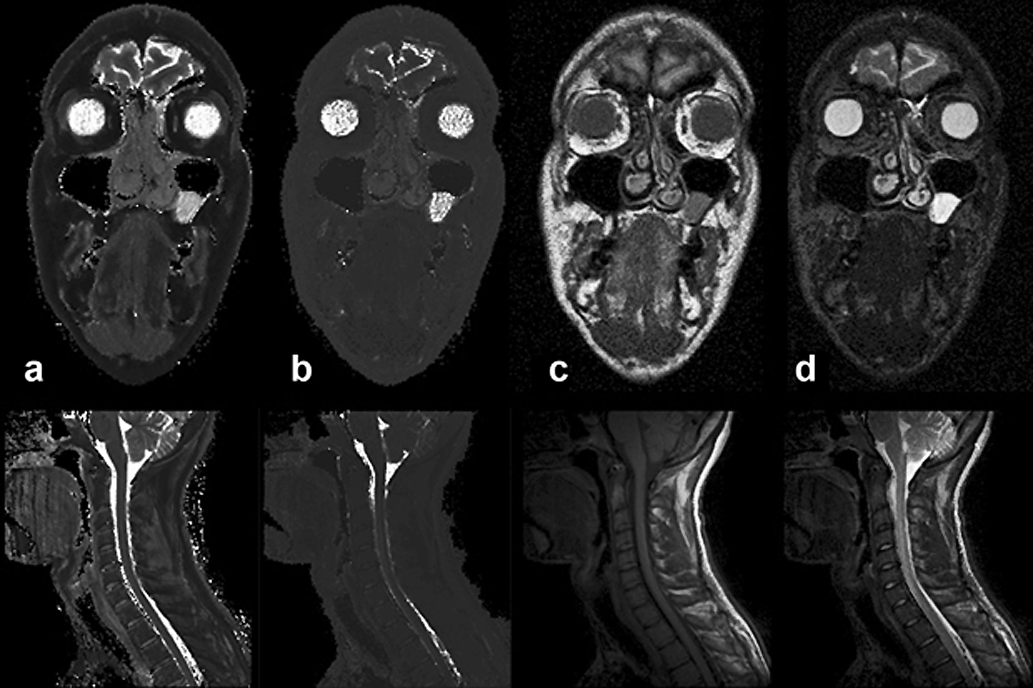

Se pueden comparar las Figuras 04-23c y d, que son imágenes potenciadas en T1 y T2, con las imágenes T1 y T2 puras de las Figuras 04-23a y b.

Figura 04-23:

(a) Imagen T1 calculada (pura), and (b) imagen T2 calculada (pura). Las Figuras (c) y (d) muestran imágenes ponderadas en T1 y T2, respectivamente.

Arriba: Imágenes de un paciente con un pólipo en la fosa paranasal izquierda.

Abajo: Imágenes de columna cervical.

Las imágenes puras de T1 y T2 tienen un valor de diagnóstico muy limitado. Las imágenes ponderadas con múltiples parámetros tienen un valor mucho mayor para el diagnóstico clínico y son comúnmente usadas en estudios de pacientes.